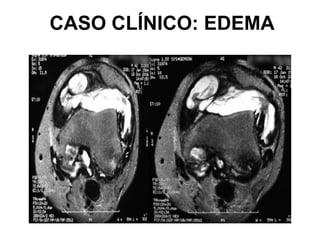

CASO CLÍNICO: EDEMA